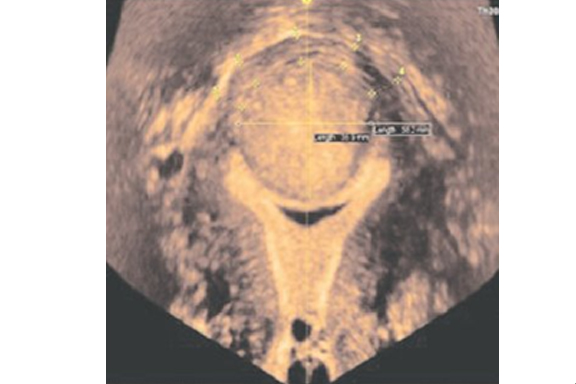

There are some of these fibroids that grow outward from the wall of the uterus into the abdominal cavity. This type of fibroid is called Subserous or Suberosal fibroids. (See picture).